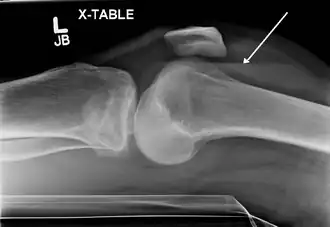

Radiographie montrant les complications liées à l'hémarthrose.